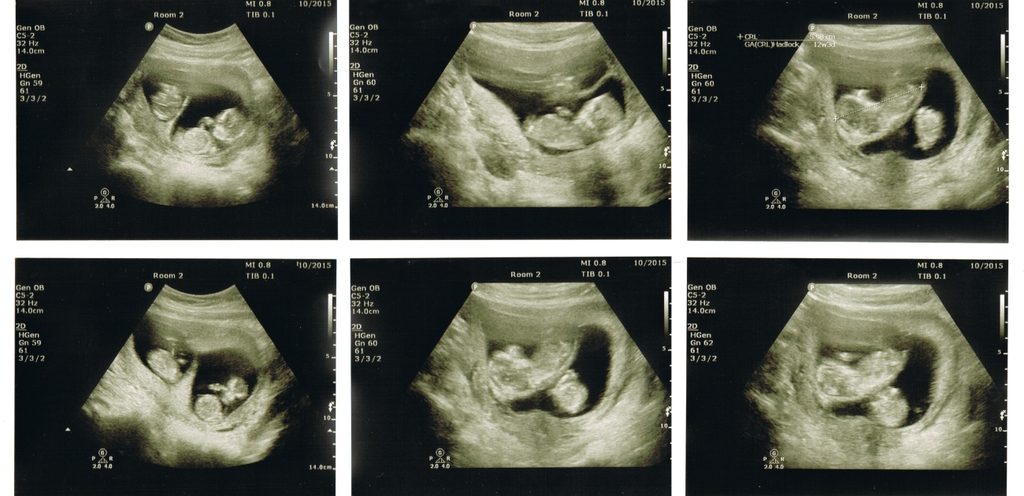

يتم حقن الإبرة التجريبية للمرأة بعد ترقب جاهزية الجريب بحيث يتم فحصه من خلال الموجات فوق الصوتية فإذا وجد أن قطر الجريب بين 18 و22 ملليمتر ستنطلق مجموعة من البويضات بعد 36 ساعة تقريبًا من حقن الإبرة.

هنالك إمكانية للحمل بتوأم بعد حقن الإبرة التفجيرية بحيث يطلق المبيض بويضتين ويتم عندها تلقيح كلا البويضتين إما طبيعيًا أو من خلال التلقيح الصناعي.

وعند الحديث عن الإبرة التفجيرية والحمل بتوأم فإن ذلك ممكنًا إذا تم إطلاق بويضتين من المبيض ومن ثم تم إجراء تلقيح لكلا البويضتين طبيعيًا أو من خلال عمليات التلقيح الاصطناعية المختلفة مثل تقنية التلقيح داخل الرحم بحيث يتم خلالها حقن كمية من السائل المنوي المعد مسبقًا ليكون بتركيز عالي وصحة جيدة للحيوانات المنوية. وهل ينجح التلقيح الصناعي للحمل بتوأم ذكور؟

أما عوارض الحمل بعد الإبرة التفجيرية بتوأم فصرح الأطباء بانها تكون خلال الأسبوع الثاني عشر من تاريخ آخر دورة شهرية، وبعض الحوامل قد تشعر بالعوارض من الأسبوع السادس من الحمل، إلى أن يتم التأكد من الحمل من خلال إجراء فحص الموجات الصوتية لتحديد إن كانوا توأم أم لا.